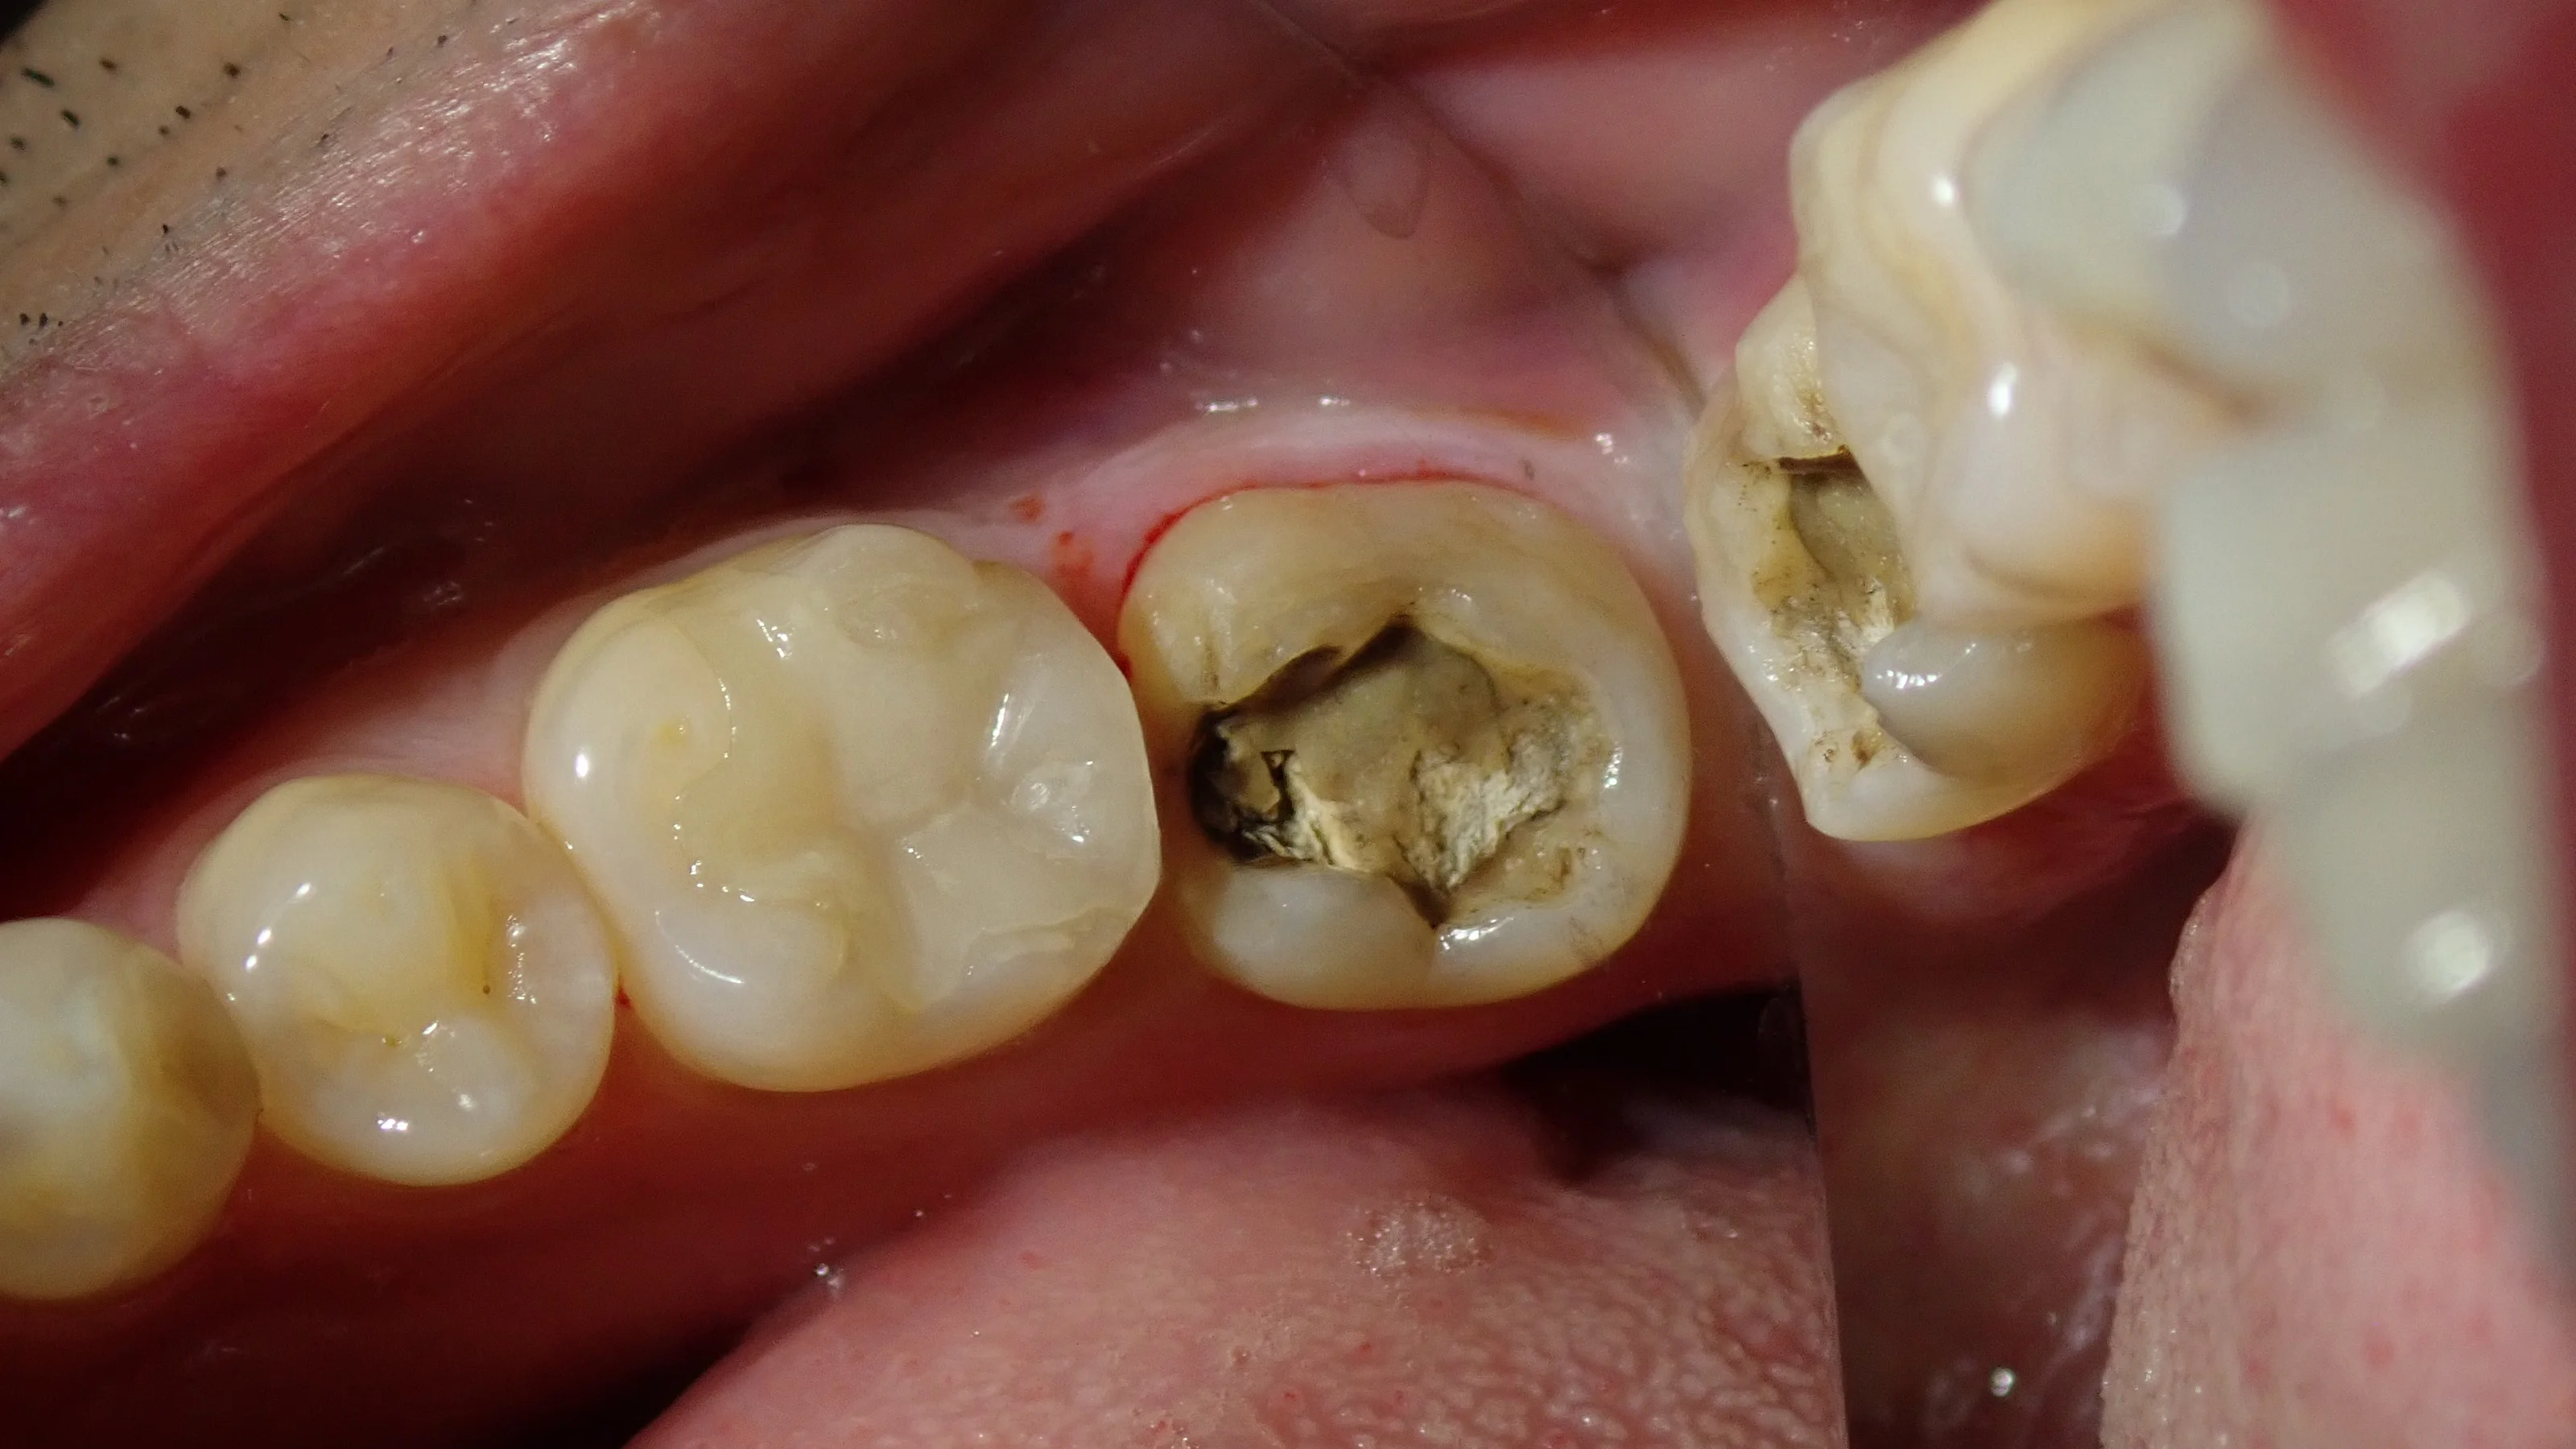

まずは術前から。

元々は金属の詰め物が詰まっていたとのことでした。

外れた下が黒くなっていて、大きな虫歯があるのが分かりますね。

こちらの記事でも書きましたが、金属の詰め物(メタルインレー)を詰めるときには多くの場合スライスカットを入れられてしまう事があります。

あまりにひどい量のスライスカットを入れられてしまうと、ダイレクトボンディングを行ったとしても、その部分が雪崩を起こすように割れてしまう事があります。

なので、メタルインレーの後の治療でダイレクトボンディングを行う時には結構注意すべき点が多いです。